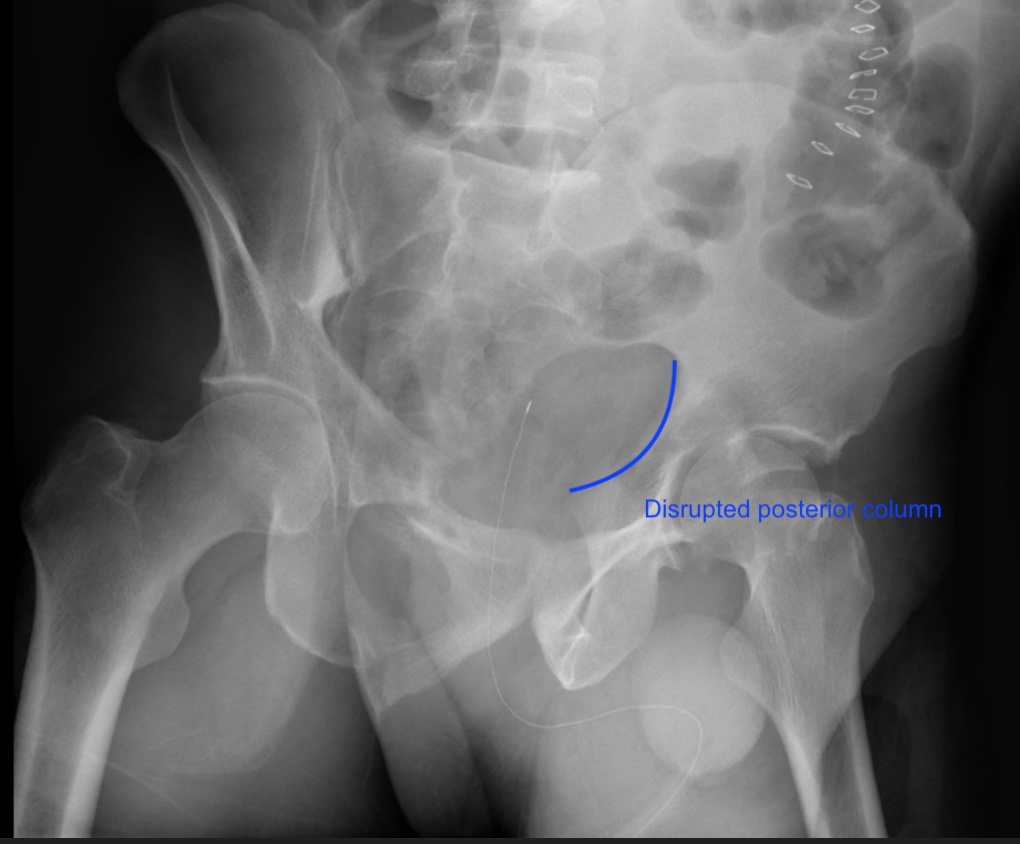

The patient has sustained a left anterior column posterior hemi-transverse acetabulum fracture. In order to properly visualize the LEFT posterior column, the most optimal radiographic Judet views would be a left iliac oblique or a right obturator oblique (these are the same image).

Acetabulum fractures are classified into 5 elementary (posterior wall, posterior column, anterior wall, anterior column, and transverse) and 5 associated fractures (associated both columns, anterior column posterior hemi-transverse, posterior wall posterior column, T-type, transverse posterior wall) patterns. Judet radiographs are very helpful in showing the extent of column and wall involvement in acetabulum fractures. These x-rays are 45-degree obliques of the hip in question and they show the profile of the obturator foramen (obturator oblique) and iliac wing (iliac oblique). To visualize the posterior column (and anterior wall), one would order the ipsilateral iliac oblique (which is equivalent to the contralateral side obturator oblique). On the contrary, the obturator oblique (and contralateral side iliac oblique) would be used to visualize the anterior column and posterior wall.

Figure A is an AP pelvis showing a left anterior column posterior hemi-transverse acetabulum fracture. Illustration A is an obturator oblique radiograph of the patient in Figure A showing an anterior column fracture. Illustration B and C are Iliac oblique radiographs showing the posterior column of the same patient.